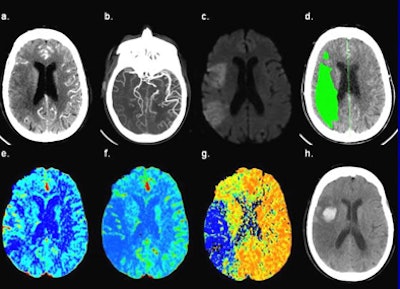

| CT images of an 81-year-old female presenting six hours after the onset of left-sided weakness and right gaze preference; not a candidate for endovascular therapy. (a) 5-mm thick CT angiography source image shows poor tissue opacification of the right middle cerebral artery (MCA) territory. (b) CT angiography maximum intensity projection image shows proximal right MCA occlusion with poor collateralization. (c) DWI-MRI shows right MCA territory infarct core. (d) Thresholded MTT lesion (rMTT > 1.3), with 140 mL total volume. (e) CBV map shows relative hyperemia (increased blood volume) of the cortical right MCA territory. (f) CBF map shows decreased flow of the right MCA territory, corresponding to the DWI lesion. (g) MTT map shows corresponding area of prolonged transit time in the right MCA territory, mean rMTT = 4.3. (h) Twenty-four hour follow-up noncontrast CT shows HT at the anterior right MCA territory. All images courtesy of Leticia Souza, MD, and Shervin Kamalian, MD. |